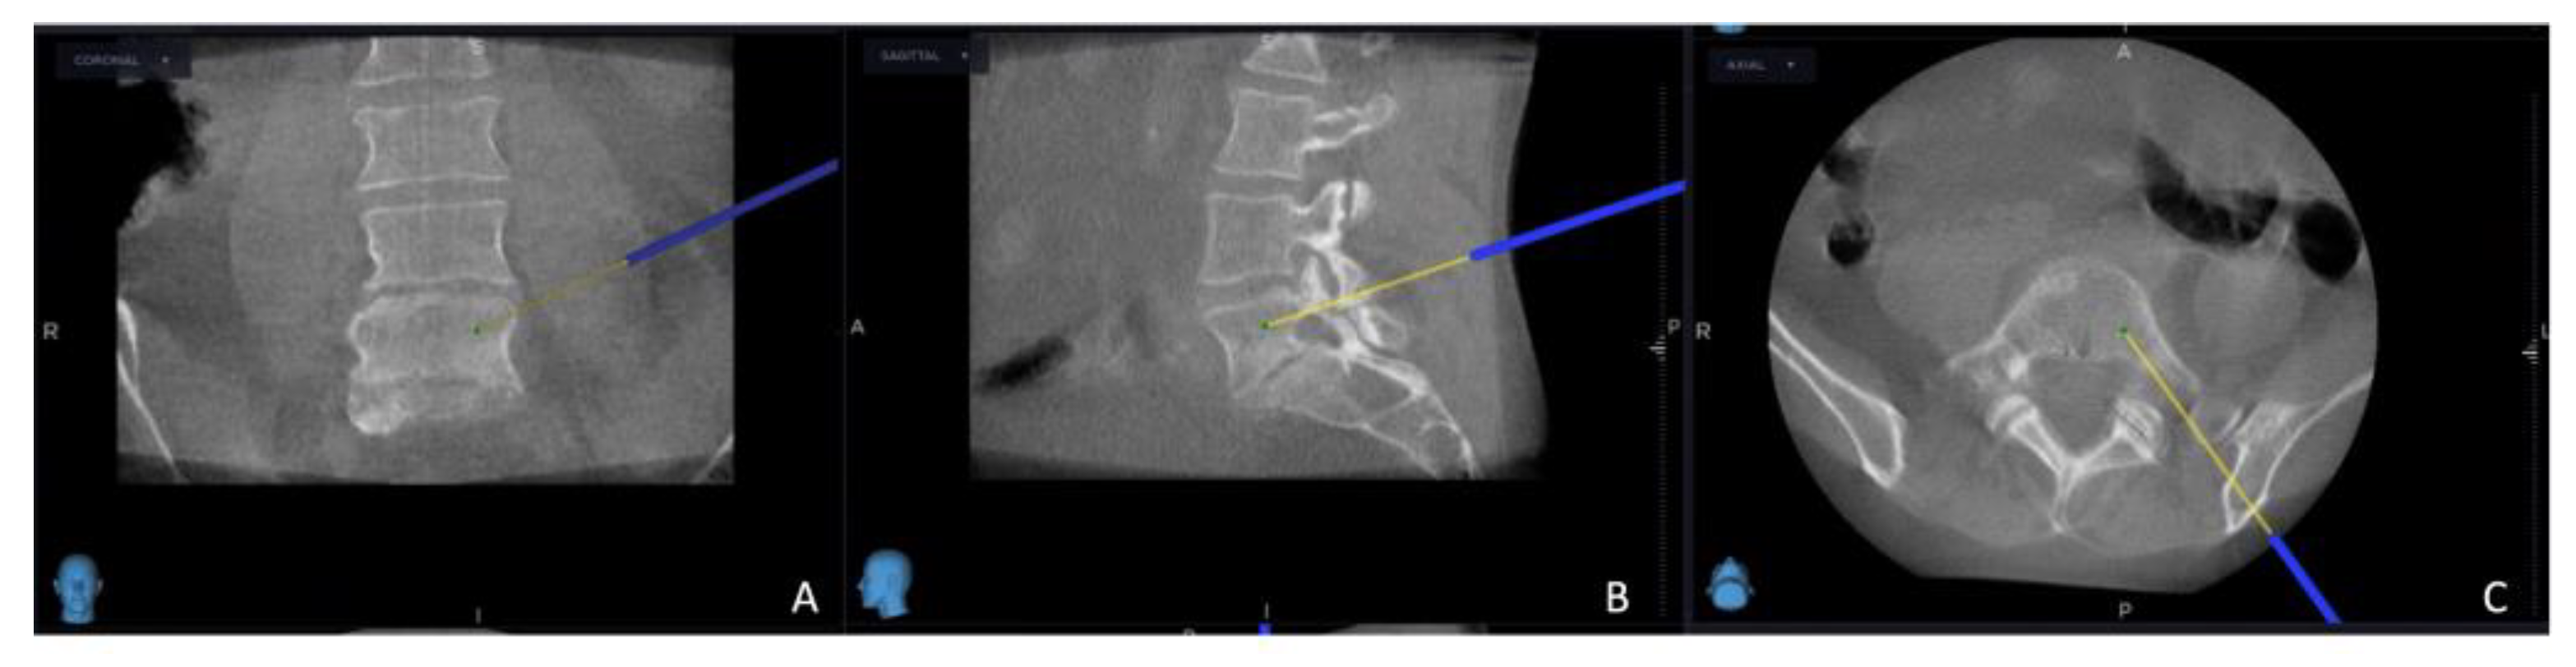

Figure 2. O-arm and MRI fused image, using the MRI image primarily, the yellow projection line, which presents the targeted site for electrode placement: (A) coronal view; (B) sagittal view; (C) axial view.

The intricate procedural sequence embarked upon with the precise determination of the initial entry point, meticulously navigated with the aid of the O-arm scan (Figure 1). Following this pivotal step, the subsequent stage involved the establishment of the targeted point for the upcoming sampling procedure guided by an MRI scan (Figure 2). The surgical roadmap for the needle biopsy procedure was delineated through the utilization of the instrument projection function This was followed by a precise 5 mm skin incision, paving the way for the needle biopsy procedure using the Johnson and Johnson 8G Vertebroplasty Needle.

The exact positioning of the needle was methodically verified by cross-referencing its location on both the O-arm and MRI scans. Concurrently, the thermostat, a crucial safety component of the procedure, was carefully introduced in close proximity to the nerve root; additionally, the electrode (Medtronic Sofamor Danek, Memphis, TN, USA) was carefully positioned, resulting in the establishment of the electrode primer location.

As the procedure advanced, a repeat O-arm scan was performed on the same spinal segment, with the main goal of verifying the biopsy's precise location, ensuring the accuracy of the electrode placement, and confirming the thermostat's position. This repeat O-arm scan was subsequently integrated with the needle biopsy plan selected from the MRI scan using the same previous "Merge Image" function. This fusion of imaging data served as the guiding framework for the precise execution of the procedure.